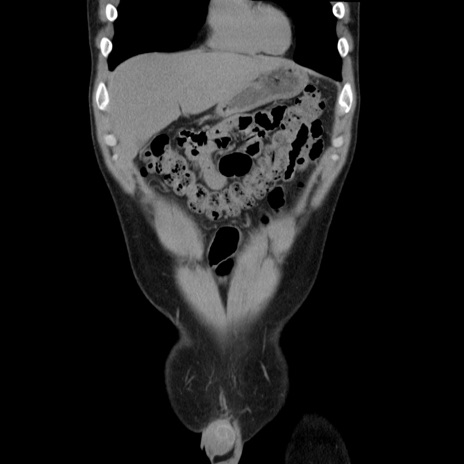

症例36(冠状断像)

【症例】20歳代 男性

【主訴】心窩部痛

【現病歴】今朝より上腹部痛あり。一旦軽快していたが再度出現したため救急要請。昨日夕に白身の魚を含む刺身を食べた。

【身体所見】BP 136/89mmHg、HR 74/min、BT 37.0℃、腹部:膨満、軟、心窩部に圧痛あり。反跳痛なし、筋性防御なし、腸雑音やや亢進あり。

【データ】WBC 17700、CRP 0.48